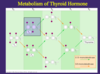

biochemical makeup of reverse T3

Reverse T3: inactive b/c you remove one inner iodine

Type I Deiodinase

5’ and 5

generate T3, Inactive T4 and T3

- Type 1 (mixed activator or inactivator) can take off 5 (inner ring) or 5’ (outer ring): present in liver, kidney, thyroid, and brain

- If 5’ à generates T3 active hormone

- If 5 (inner) à generates rT3 (inactive)